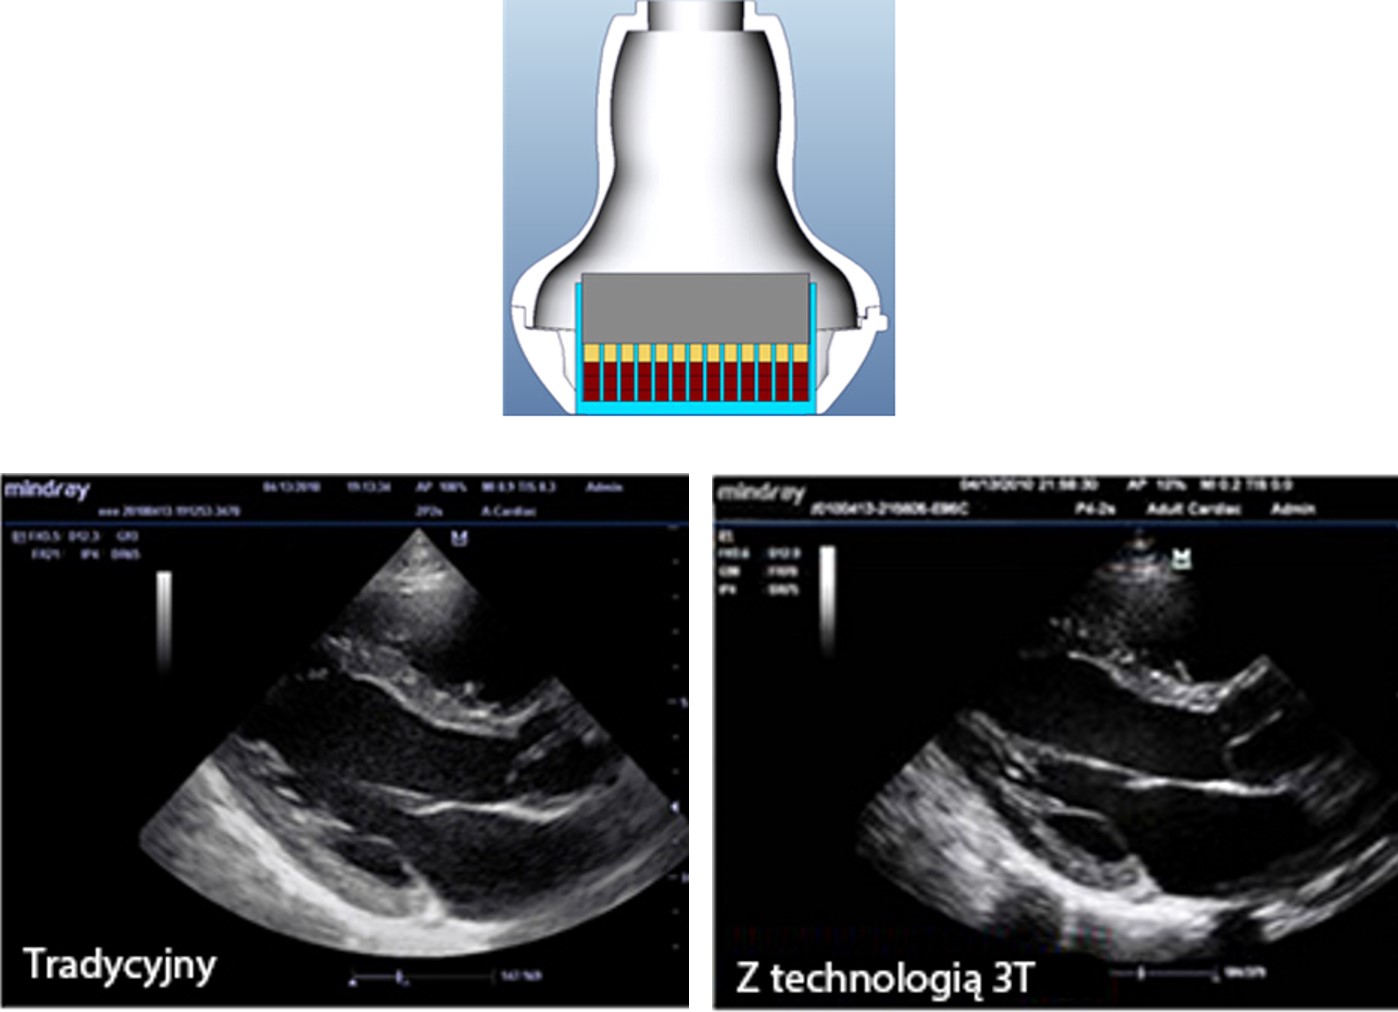

Sondy wykonane w technologii 3T

Opatentowana technologia wykorzystywana w sondach Firmy Mindray zwi?ksza zakres obrazowania i wydajno?? transmisji.

┬Ę?Dzi?ki potr├│jnej warstwie dopasowania uzyskujemy lepsz? czu?o??, szerszy zakres obrazowania i lepszy wsp├│?czynnik sygna? / szum (S/N)

┬Ę?konstrukcja z ca?kowitym odci?ciem wp?ywa na zmniejszenie zak?├│ce┼ä, lepsz? kierunkowo?? i popraw? rozdzielczo?ci

┬Ę?Kontrola termiczna polepsza transmisj? akustyczn?.